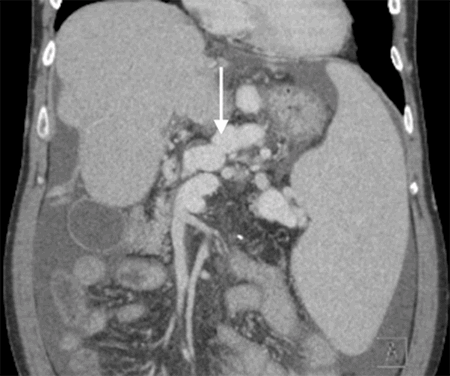

Figure 5. Coronal CT Abdomen Ten Days Postoperatively, Demonstrating Patent Left Gastric-Portal Vein Anastomosis (White Arrow Indicates Portal Vein And Black Arrow, Left Gastric Vein). Published with Permission

Postoperative doppler showed velocity of 135 cm/s in the main portal vein, and CT depicted patent left gastric-portal anastomosis. His postoperative course was fairly uncomplicated, except for a seizure. There were no signs of posterior reversible encephalopathy syndrome (PRES) on CT, and the patient returned to baseline quickly. The patient was malnourished and required nasoduodenal tube feeds for supplemental nutrition. His appetite improved, and the patient was discharged to a rehabilitation facility on postoperative day 17. One week later, the patient was hospitalized for hyperglycemia and superficial surgical site infection, which required wound opening and wound VAC placement. The endocrinology service managed his uncontrolled diabetes mellitus, which was complicated due to corticosteroids and tacrolimus. His diabetes control was optimized, and the patient was discharged with a wound VAC, which was discontinued one month after discharge. The patient demonstrated decreased renal function (creatinine 2.2, preoperative baseline 1.0) throughout his postoperative course, which was managed by nephrology. Repeat liver Doppler ultrasound three months postoperatively demonstrated continued patency of the portal-gastric anastomosis.